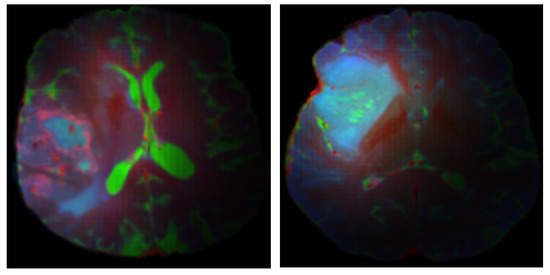

IDH Mutation Assessment in Gliomas from Anatomical MRI Using Deep Learning: A Comparative Analysis of Centralized and Federated Learning Frameworks

Background/Objectives: Isocitrate dehydrogenase (IDH) mutation is a key prognostic indicator in diffuse gliomas; however, it is clinically determined from invasive tissue sampling. Non-invasive preoperative identification of IDH mutation from routine anatomical MRI could support treatment decision making. This study evaluated deep learning models [...] Read more.

Background/Objectives: Isocitrate dehydrogenase (IDH) mutation is a key prognostic indicator in diffuse gliomas; however, it is clinically determined from invasive tissue sampling. Non-invasive preoperative identification of IDH mutation from routine anatomical MRI could support treatment decision making. This study evaluated deep learning models for IDH mutation detection using routine anatomical MRI (post-contrast T1-weighted (T1c), T2-weighted, and fluid attenuated inversion recovery (FLAIR) MRI) and quantified how tumor-focused image preprocessing and different training schemes, centralized learning (CL) versus federated learning (FL) with alternative aggregation strategies, affected model performance. Methods: Anatomical MRI from 501 diffuse glioma patients in the UCSF Preoperative Diffuse Glioma MRI (UCSF-PDGM) dataset was analyzed using a deep learning classifier built on a 2D U-Net encoder, with age and sex included as covariates. Two methods of tumor-focused image preprocessing, Naïve Soft Filtering (NSF) and Gradient-Based Soft Filtering (GBSF), were compared. Centralized learning (CL) was benchmarked against federated learning (FL) using Federated Averaging (FA) and Federated Trimmed Mean (FTM) aggregation strategies. Model performance was compared in terms of accuracy, precision, recall, F1 score, specificity, and the area under the receiver operating characteristic curve (ROC-AUC). Results: The CL model with NSF achieved the best test performance (accuracy = 0.949, F1 = 0.951, ROC-AUC = 0.971), with NSF consistently outperforming GBSF. FL’s performance decreased relative to CL’s, but the FA strategy outperformed FTM (FTM accuracy = 0.915 vs. FA accuracy = 0.949), which indicates that the FL aggregation strategy has an influence on model performance. Conclusions: Deep learning applied to routine anatomical MRI could classify IDH mutation status with high accuracy. Context-preserving image preprocessing with NSF substantially improved performance across training schemes. FL provides a privacy-preserving alternative to CL, but incurs a measurable performance degradation that is sensitive to the choice of aggregation strategy. Full article